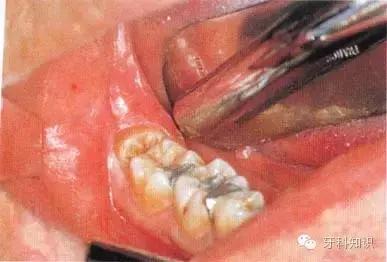

例一

a第Ⅱ类,b分类中位阻生。左下颌第三磨牙阻生,位于黏膜下。磨牙后区切开后,作近中切口,使用12号刀片沿牙龈扇贝状外形切透龈沟至牙槽嵴顶,避免将龈乳头切除。图中近中切口延长至第二前磨牙,便于翻瓣,更好地显露磨牙后区的骨质